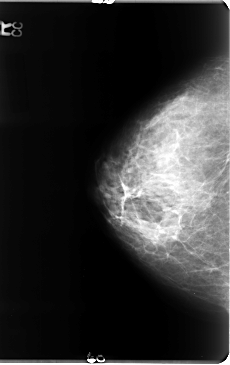

B_3072_1.LEFT_CC

LEFT_CC LINES 4720 PIXELS_PER_LINE 2840 BITS_PER_PIXEL 12 RESOLUTION 50 OVERLAY

FILE: B_3072_1.LEFT_CC.OVERLAY

TOTAL_ABNORMALITIES 1

ABNORMALITY 1

LESION_TYPE MASS SHAPE IRREGULAR MARGINS OBSCURED-ILL_DEFINED

ASSESSMENT 3

SUBTLETY 3

PATHOLOGY MALIGNANT

TOTAL_OUTLINES 1

BOUNDARY